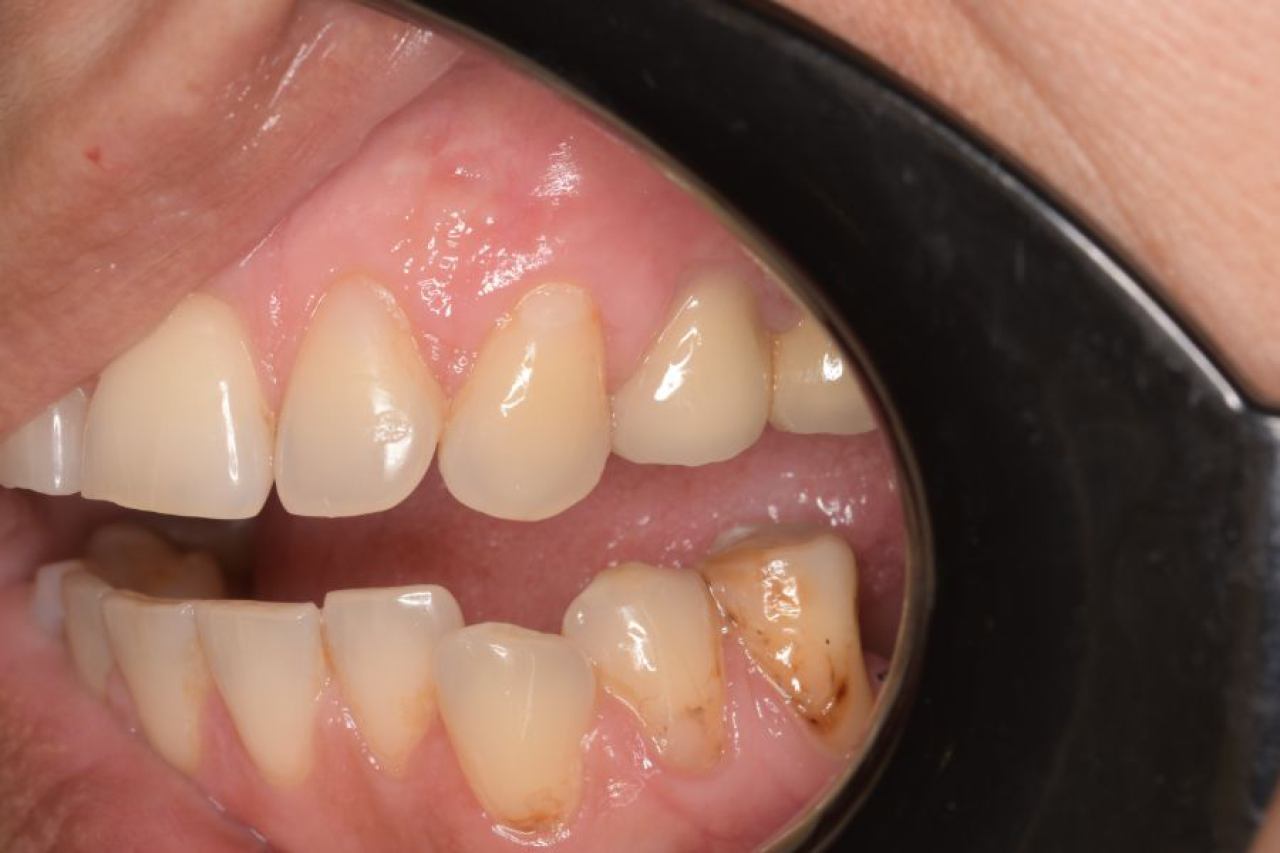

Parodontologija i kirurgija

Parodontologija je grana dentalne medicine koja se bavi zdravljem potpornih struktura zuba (parodonta). Parodont se sastoji od zubnog mesa (gingiva), kosti i vlakana koja vežu zub za kost (parodontalni ligament).

Ovo je grana kojoj Marković Dental Clinic pridaje puno pažnje jer je vrlo kompleksna i bitna za cijelo oralno zdravlje.

Regeneracija kosti i mekog tkiva

Gingivalne recesije u narodu poznatije kao „povlačenje zubnog mesa" moguće je korigirati kirurškim zahvatom te vratiti gingivu (zubno meso) u fiziološki položaj mikrokirurškim tehnikama. Zahvati koje odrađujemo kod regeneracije kosti i mekog tkiva su podizanje dna sinusa (sinus lift) i nadomještanje izgubljenog volumena kosti (augmentacija kosti, regeneracija kosti).